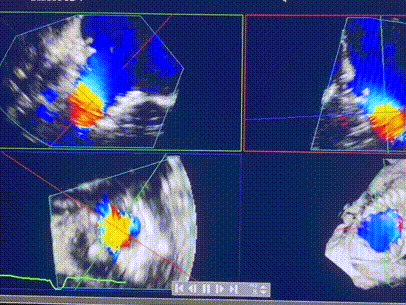

術(shù)前超聲提示重度三尖瓣反流

術(shù)中輸送器在超聲引導(dǎo)下調(diào)整位置

手術(shù)在全麻狀態(tài)下進(jìn)行。術(shù)者采用經(jīng)右側(cè)頸靜脈入路的方式將輸送器送入患者心臟內(nèi),在TEE及DSA引導(dǎo)下調(diào)整輸送器頭端角度,使得輸送器與三尖瓣瓣環(huán)平面垂直。在輸送器進(jìn)入右心室后釋放室間隔錨定裝置,而后釋放瓣葉夾持件(2個(gè)耳片結(jié)構(gòu))成垂直狀態(tài)。在TEE及DSA確定夾持件固定至三尖瓣葉根部且位于右室側(cè)后釋放人工瓣心房側(cè)盤片。隨后調(diào)整瓣膜同軸性以及室間隔錨定件位置(貼合室間隔),前推藏針管并固定,進(jìn)而釋放室間隔錨定裝置,并再次確認(rèn)瓣膜位置、穩(wěn)定性及同軸性,合攏輸送鞘后撤出輸送器,完成LuX-Valve Plus人工三尖瓣瓣膜的植入,僅殘余微量瓣周漏。且經(jīng)手術(shù)中心電生理團(tuán)隊(duì)評(píng)估,病人的起搏器和ICD功能沒有受到影響。